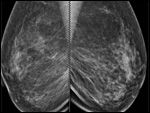

Digital mammography shows area of calcifications (Figure 1a-b). Magnification views demonstrate intraductal pleomorphic microcalcifications in the right 11:00 area (Figure 1c).